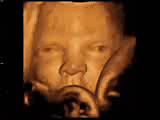

實時4D胎兒造影

成長中的胎兒